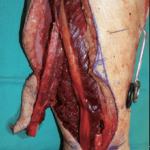

The conventional approach is completely based on the expertise and experience of the clinician. It includes simultaneous resection of the mandibular pathology as well as the harvesting of the fibular graft. This is done on the basis of manual measurements, making it not 100% accurate. The resection is then followed by the surgical reconstruction of the mandible by harvesting the fibular graft (image 3). Before the placement of implants the patient is asked to wait for a period of 3-5 months for the graft to get accepted.